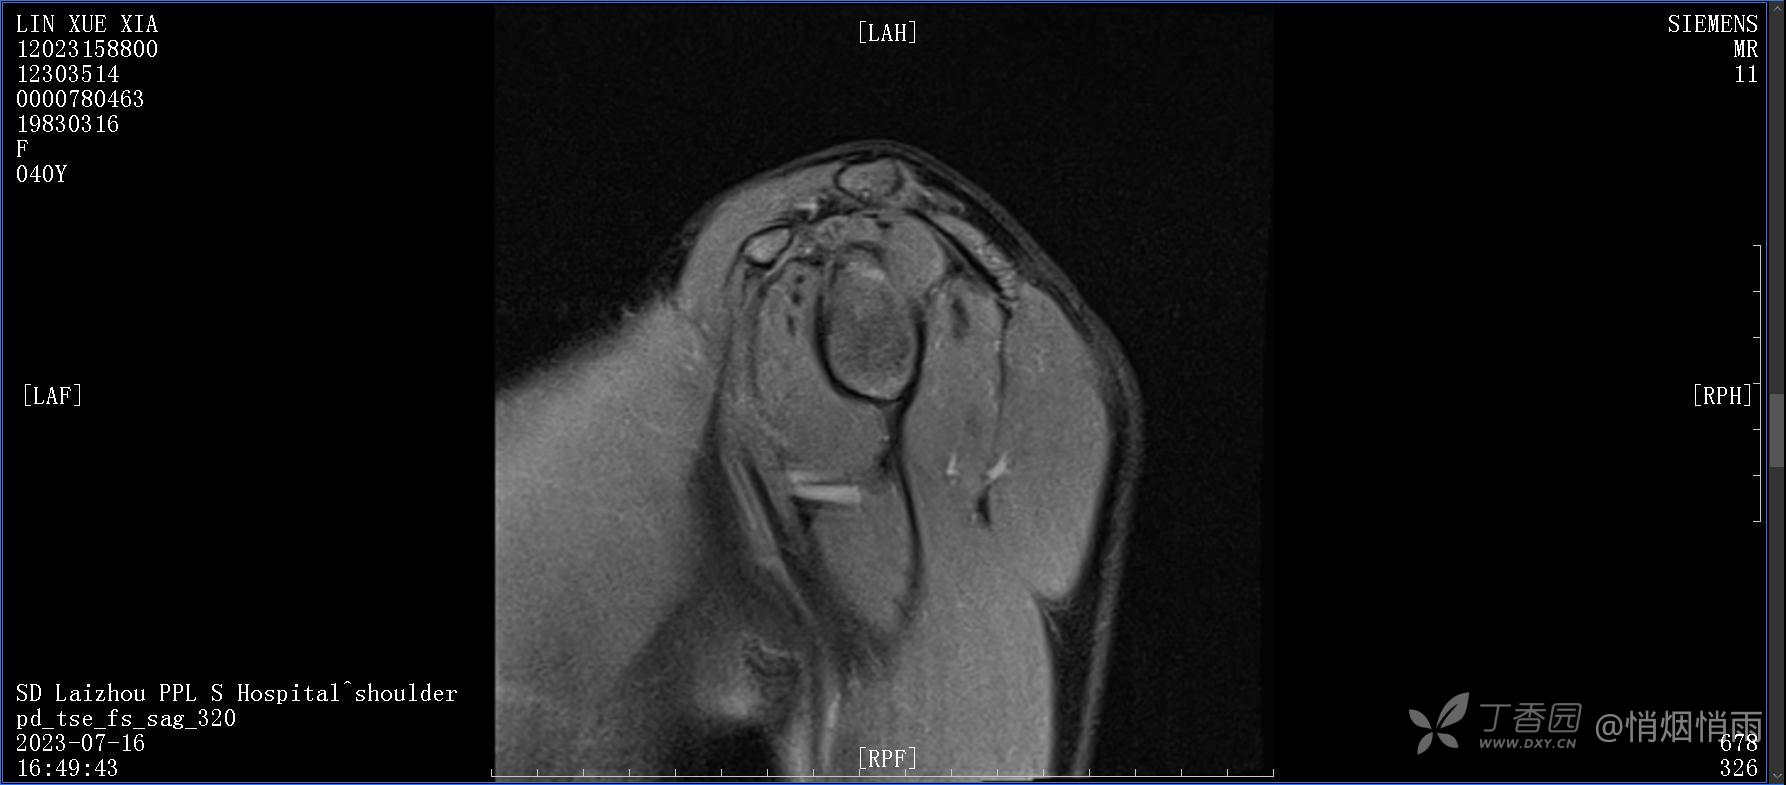

查体:右肩关节局部轻度肿胀,肩胛区压痛明显,痛处不固定,肩关节痛性活动受限,jobe test(+),lift -off test(+),中指、环指感觉较余指减退,余肢端感觉及血运情况可。

目前的诊断,暂时依据辅助检查诊为肩袖损伤,但是患者疼痛的性质和特点,却不是单纯的肩袖损伤所致。考虑过胸廓出口综合征,但是该疾病会出现肩胛区的疼痛吗?(由于考虑到费用的问题,没再进行下一步的检查)带状疱疹会有如此的症状吗?